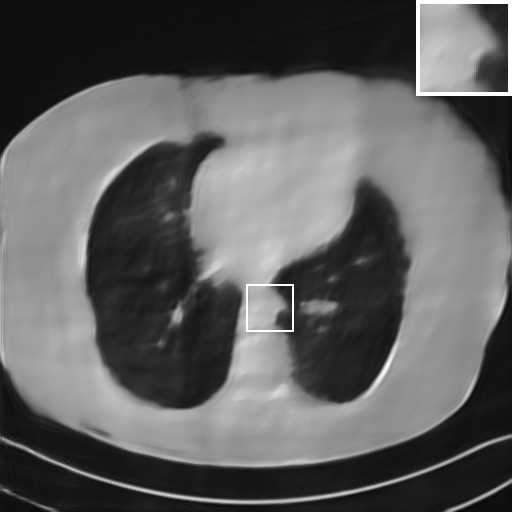

Fig. 4 presents the reconstruction results and residual images obtained by different methods for limited-angle reconstruction. As can be seen, the learning-based methods outperform the direct method and TV model, which exhibit serious artifacts in the missing angle region. Although the denoiser introduced by the FBP-Unet can somehow deal with the noises, the result still presents obvious artifacts. Compared to the SIPID, PD-net and FSR-nets, our LRIP-net1/2 can better preserve the image details and edges with less information left in the residual images. Thus, both the quantitative and qualitative results confirm that the low-to-high double-resolution strategy can improve the reconstruction accuracy for the limited-angle reconstruction problem.

We observe that the low-resolution image prior plays an important role in our method. More specifically, we compare the results of our LRIP-net with respect to different low-resolution priors, which are obtained by down-sampling rate of 1/2, 1/4, and 1/8, respectively. As can be seen in Table III, the best reconstruction results are obtained with the image prior reconstructed by the down-sampling rate of for 150∘, 120∘ and 90∘ limited-angle reconstruction. The visual comparison based on different image priors are also provided in Fig. 5, where obviously less artifacts are left in the reconstruction image by LRIP-net1/8. By comparing the running time, it is easy to see that the smaller the low-resolution image prior, the faster the LRIP-net works.